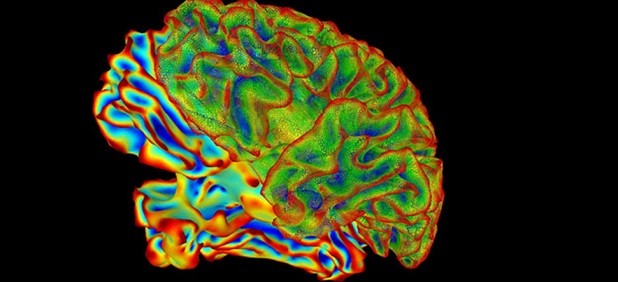

نوروسافاری | محققان کالج پزشکی بیلور در آمریکا با استفاده از موشها مدلی را برای مطالعه پیامدهای عفونت قارچی بر مغز توسعه دادند. در این تحقیقات مشخص شد موشها پس از ۱۰ روز عفونت قارچی را از بین میبرند اما آثار التهابی و اختلال حافظه حداقل تا ۲۱ روز بعد باقی میماند.

به گزارش نوروسافاری از کالج بیلور، در این تحقیقات کاندیدا آلبیکاس که نوعی قارچ متداول در بدن انسان است، به جریان خون موش ها تزریق شد و با انجام بررسی های دقیق مشخص شد این نوع قارچ قابلیت عبور از سد خونی مغزی را دارد. سد خونی مغزی یک مکانیزم دفاعی بسیار توانمند است که مانع ورود انواع مولکول های ریز و درشت و همچنین انواع میکروارگانیسم های خطرناک به مغز می شود.

قارچ ها پس از ورود به مغز موجب تحریک سلول های ایمنی موسوم به میکروگلیا می شوند. این سلول ها در واکنش به قارچ بسیار فعال می شوند و شروع به هضم قارچ ها می کنند. همچنین مولکول هایی را تولید می کنند که یک واکنش التهابی ایجاد کرده و قارچ ها را در ساختارهای گرانول مانندی درون مغز به دام می اندازد.

شکل گیری این تومورهای گرانولوم موجب بروز اختلالات موقتی در حافظه موش ها می شود. نکته جالب توجه این است که ساختارهای گرانولومی که در واقع تومورهای متشکل از جوانه های گوشتی هستند، ویژگی هایی مشابه پلاک های ایجاد شده در مغز بیماران مبتلا به آلزایمر دارند. این نتایج موید نتایج تحقیقاتی است که نشان دهنده آثار نامطلوب عفونت مزمن کاندیداآلبیکاس بر سیستم عصبی هستند. در این تحقیقات مشخص شد موش ها پس از ۱۰ روز عفونت قارچی را از بین می برند اما آثار التهابی و اختلال حافظه حداقل تا ۲۱ روز بعد باقی می ماند.